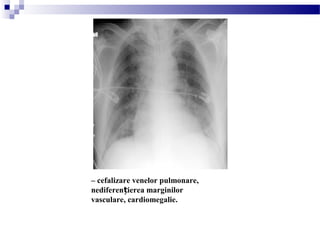

EDEMUL PULMONAR

– cefalizare venelor pulmonare,

nediferen ierea marginilorț

vasculare, cardiomegalie.